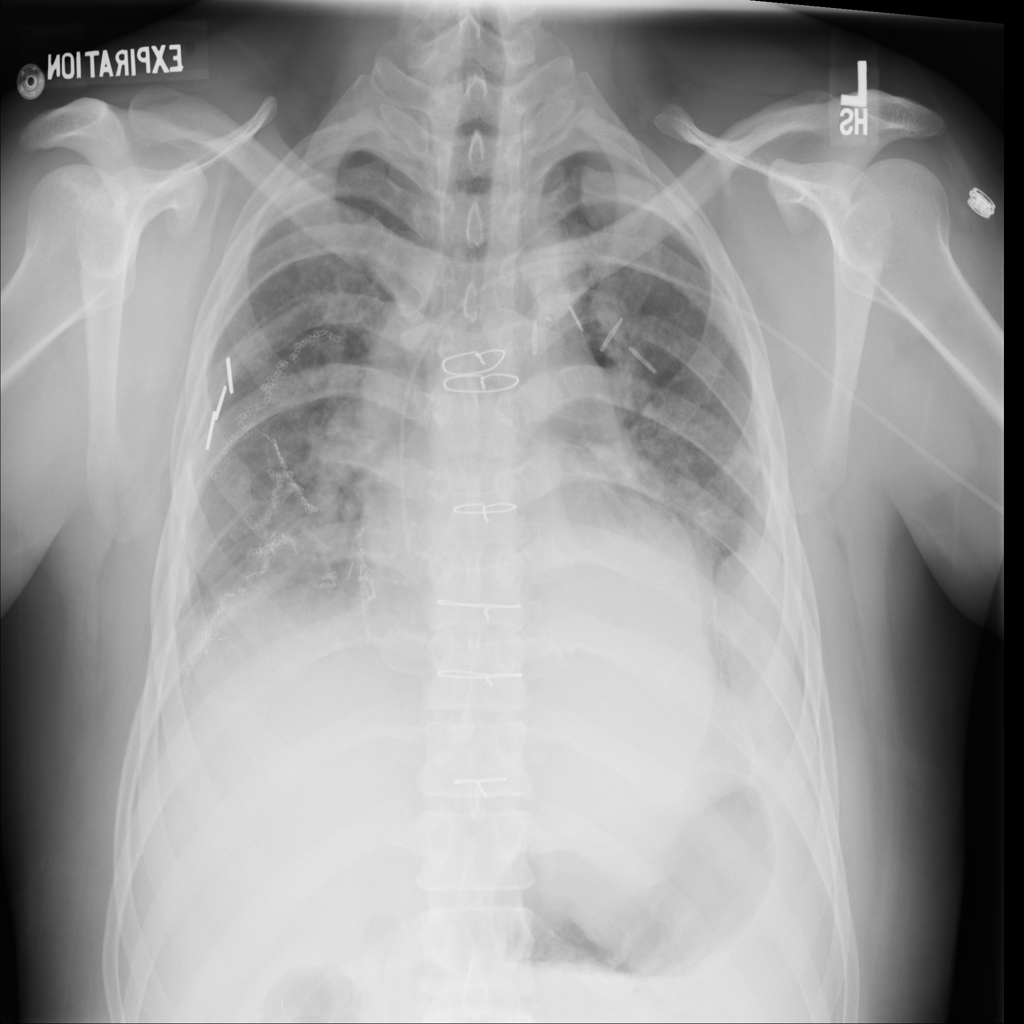

PAT-4639 · IMG-024Mass

PAT-4639 · IMG-024

AP